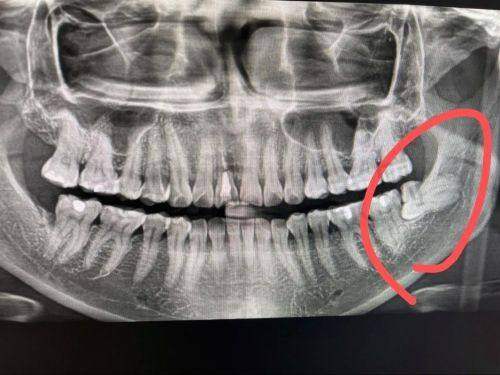

江宁牙管家口腔推出的阻生智齿拔除641元起的优惠活动,吸引了众多有智齿困扰的市民关注。阻生智齿不仅会引发疼痛,还可能影响口腔健康,及时拔除至关重要。那么江宁牙管家口腔在阻生智齿拔除方面究竟有何优势呢?下面为您详细介绍。

江宁牙管家口腔此次推出的阻生智齿拔除641元起的价格,是根据智齿的生长情况和拔除难度来定价的。一般来说,智齿位置比较正,拔除难度较低的,费用可能在500 - 1000元之间;而如果智齿是阻生齿或者位置较深,需要切开牙龈或磨除部分牙槽骨,费用会高一些,大概在1000 - 3000元不等。这种灵活的定价方式,能够让患者根据自身情况选择合适的治疗方案,既确保了治疗成效,又能在一定程度上减轻患者的经济负担。